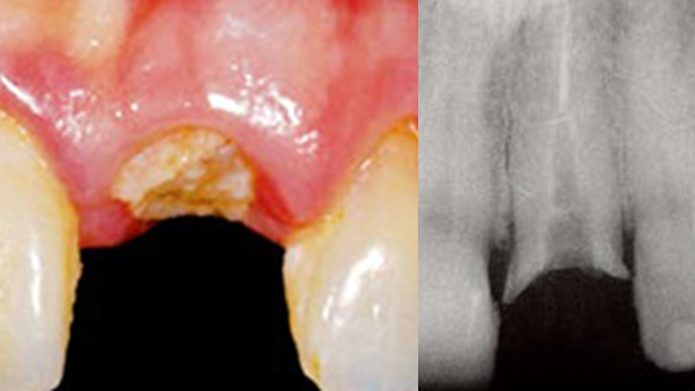

Clinical case: Replacement of fractured central incisor (#11) with immediate implant

& Root Membrane Technique

- Courtesy of Dr. Miltiadis Mitsias, Greece -

Keywords

AnyRidge, Root Membrane Technique, retrospective study, long-term study, immediate implants, bone resorption, bone preservation, Dr. Miltiadis Mitsias,survival, success, maxillary anterior, single replacement

Products:

AnyRidge implant system, Root Membrane kit

Reference

The Root Membrane Technique: A retrospective clinical study with up to 10 years of follow-up./Implant Dent. 2018 Oct;27(5):564-574

https://www.ncbi.nlm.nih.gov/pubmed/30161062